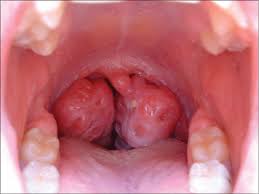

Enlarged Tonsils and Mouth Breathing in Children

Tonsils are part of the immune system. Their job is to monitor bacteria, viruses, and particles entering the airway.

The tonsils now become the first line of defense — and they grow larger.

Enlarged tonsils are often not simply a disease. They are frequently a protective response to chronic mouth breathing.